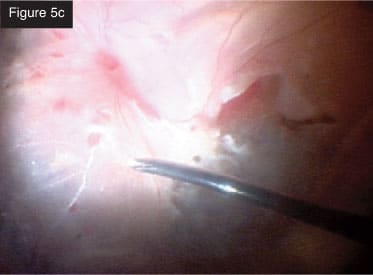

Final view. CASE 5: Severe PVR with subretinal membranes. In this case, the eye was filled with silicone oil. The eye already had several surgeries, but the conjunctiva looked good. I removed the oil (Figure 5a) and then went under the retina to remove large sheets of subretinal membrane that had collected all the way around (Figures 5b and 5c). While doing this case, I was impressed with the lighting on the CONSTELLATION® System and how well I could visualize tissue at all times. I performed a fluid-air exchange and aspirated with the same probe through the retinotomies. After applying laser to the breaks, I injected silicone oil. I performed all of these maneuvers in a smooth, seamless, efficient manner with minimal exchange of instruments and with total IOP control throughout. These few cases represent the many complex pathologies that can be treated using the CONSTELLATION® Vision System.

Subretinal membrane removal.